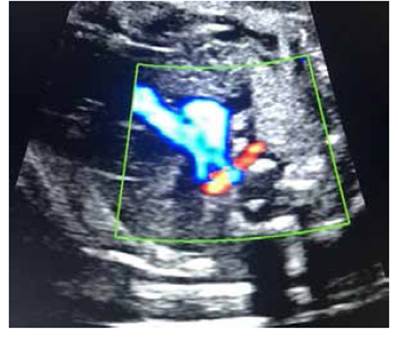

A las 24 semanas se realizó o'Sullivan, que fue normal. A las 28 semanas recibió la vacuna anti tos ferina protocolizada en el Sistema Nacional de Salud Español) La ecografía a las 33 semanas 1 día mostró feto en cefálico, crecimiento adecuado, líquido amniótico normal, movimientos fetales normales. Se realizó nueva ecocardiografía fetal, visualizándose ARSA; no se vio patología estructural asociada cardiaca ni extracardiaca. Doppler de la arteria umbilical con índice de pulsatilidad dentro de valores normales. Figura 3.